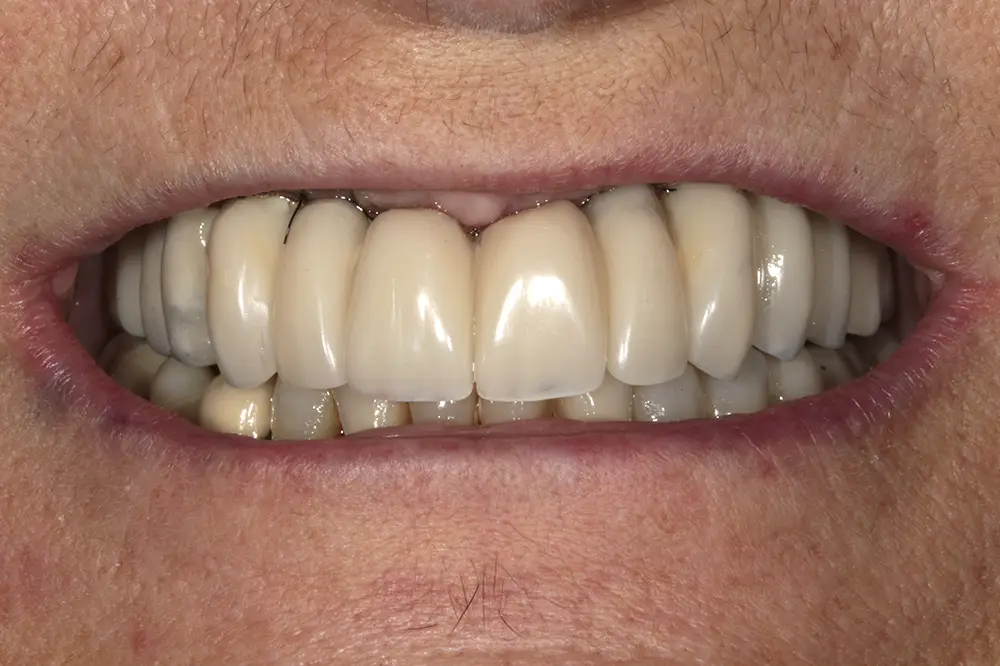

Para los sectores posteriores, se fabricaron estructuras mediante fresado CAD/CAM del mismo modo que la barra anteriormente descrita, con la diferencia de que sobre ellas se colocó un recubrimiento de cerámica (figs. 47-49). La paciente continúa en seguimiento, sin evidenciarse pérdidas óseas significativas en ninguno de los implantes estrechos y cortos que conforman la restauración de todo el maxilar superior tras tres años de carga de la prótesis definitiva (y hasta 4,5 de la carga de los implantes de la fase inicial de carga inmediata) (fig. 50).

Figs. 47 y 48. Prótesis terminadas, colocadas en la paciente.